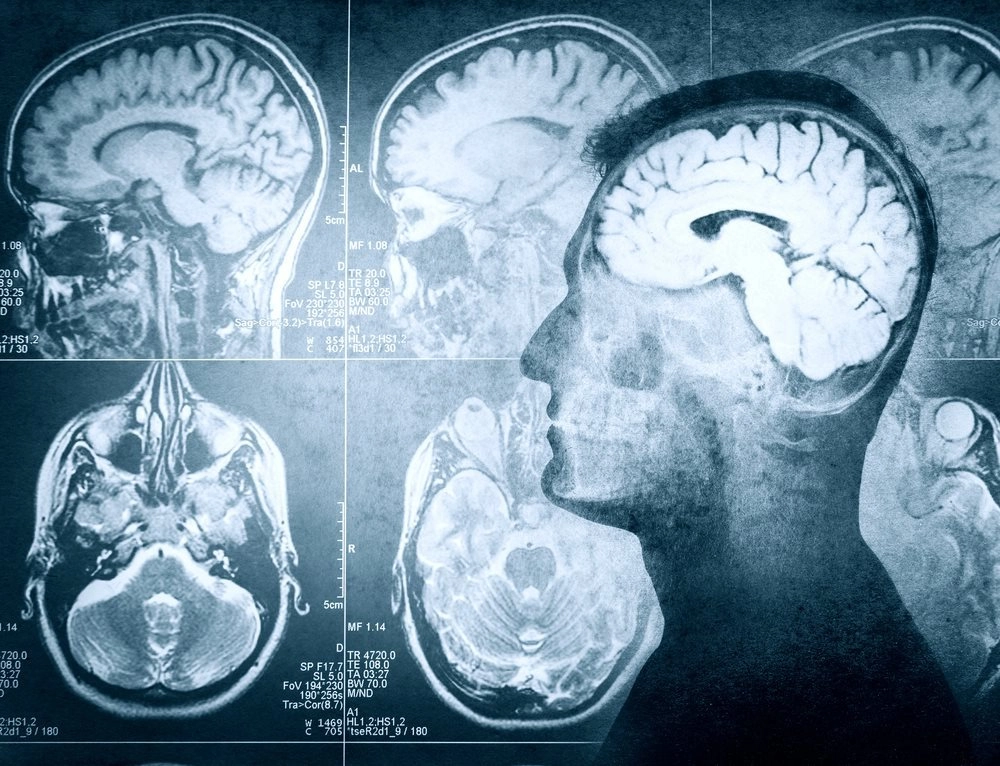

На наш мозг приходится приблизительно 2% веса тела, однако потребляет он 20% от суточной нормы калорий.

Мозг человека регулирует силу мышц. Если бы мышцы ног напряглись в полную силу, они бы могли сломать бедро. Человеческое тело сильное, но может навредить самому себе.

Мозг человека продолжает попытки оживить тело еще долгое время после остановки сердца. Учеными была зафиксирована мозговая активность спустя 30 часов после смерти пациента.